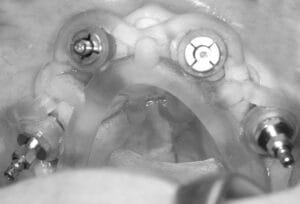

Step 4 – Surgery day

On the day of treatment, you’ll be welcomed into our central London clinic and we will explain the surgery again step by step. Your implant guide ensures the implant is placed in exactly the pre-planned location. Sedation is available for anxious patients who prefer a more relaxed experience.